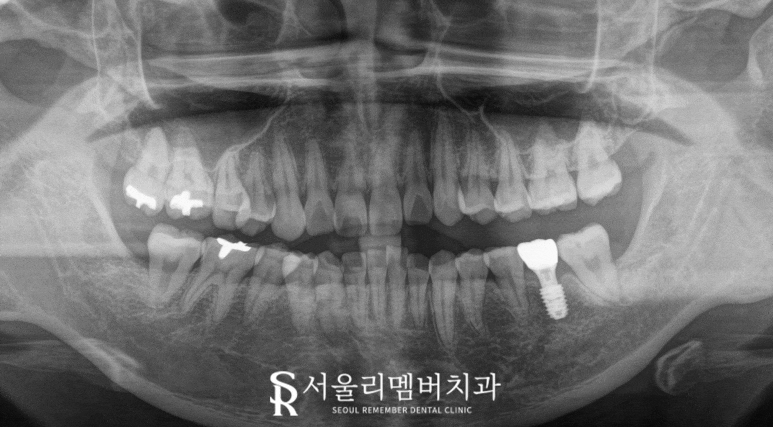

모든 진료가 끝난 모습을 보겠습니다.

2024.11.30

임플란트 식립 후에는 골 유착 과정을 통해

충분한 고정력이 나왔다면

그 위로 보철을 올리게 됩니다.

일반적으로

하악은 2-3개월의 치유 기간이 필요하며,

이후 보철물 장착을 통해

저작 기능과 심미성을 회복하기까지는

3~4개월 정도 소요됩니다.

제3대구치 역시 뽑고 난 이후에도

발치와의 치유 과정이 필요한데,

초기에는 혈병 형성,

육아조직 형성이 이루어지고,

점차 골 형성이 진행되어

최종적으로 이를 뽑은 자리가 아물게 됩니다

임플란트 보철이 잘 안착되었고,

주변 잇몸 조직도 잘 적응하였으며

이를 뺀 자리도 잘 아물었으니

이제는 구강위생관리를 철저히 해주면 되겠습니다.